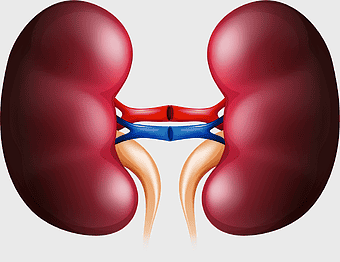

urinary system anatomy, kidney function illustration, ureter diagram, bladder infection symptoms, renal system health, excretory function chart, genitourinary medical diagram -

kidney anatomy, human kidney illustration, kidney cancer awareness, kidney organ diagram, renal system structure, medical kidney image, urinary system components -